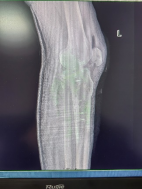

患者56歲男性,外傷致左踝部疼痛出血、腫脹畸形、活動受限,X線片顯示左脛腓骨遠端碎折,骨折斷端嵌插,骨折波及關(guān)節(jié)面,左脛骨近端內(nèi)側(cè)骨質(zhì)連續(xù)性中斷。

控制機器人牽引斷端,可見關(guān)節(jié)間隙恢復。